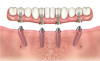

For surgical placement the dual-axis root form fixture is connected to an angle-correcting mount having a reciprocal inclination with the angulated platform of the implant enabling the fixture to be inserted in a straight axis (Figure 5 and Figure 6). An orientation dimple shows the rotational position of the implant in the bone.

Fig 5. Dual-axial implant.

Figure 5

Fig 6. Dual-axial implant.

Figure 6